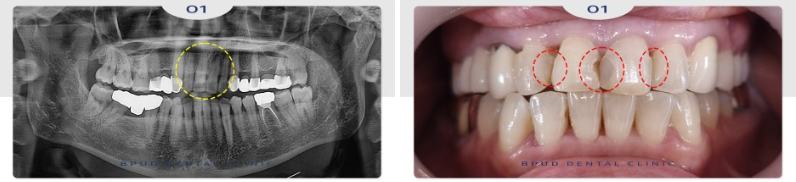

따라서 우식으로 인한 병소가 보이는

가장 큰 앞니 두 개만 신경치료를 진행하여

4개의 치아를 연결하는 보철을

진행하시기로 계획을 수립하였습니다.

24.11.08

앞니 두 개 신경치료를 마친 모습입니다.

근관치료라고도 불리는 신경치료는

내부의 신경, 혈관 및 기타 세포 조직을

제거한 후 그 공간에 다른 재료를 밀봉한 후

치아 전체에 크라운을 씌우는 방식으로 이루어져

기능을 유지시키는 시술인데요.

환자분들마다 신경조직의 위치나 모양,

치아의 위치에 따라 뿌리의 개수가 달라

방법이 달라지기 때문에 난이도가 높은

치료에 속합니다.